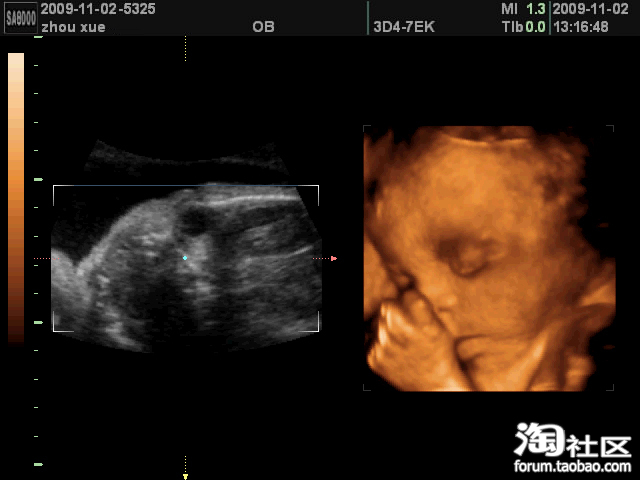

他先是用小手挡着嘴,不让我们看,高高的鼻子精巧的嘴型与我极像

我们特别想看看他的嘴,别有人什么裂的,他却像是有意的,总是一只手在嘴上挡着,照了一会惹急我了,一巴掌拍在肚皮上,清脆的一声响后,手终于拿开了,嘿嘿,当时把在场的人都看傻了,他们准是想我这当妈的够狠的,其实不是这样的。

我们平时在家的时候会这样做游戏的,宝宝有时犯懒不爱动,可是我们每天睡前都要玩的,他不理我,我就在肚皮上拍一下,他听到声音就会和我玩了。

这不吗,他动了以后,嘴就露出来了,长得很好哦